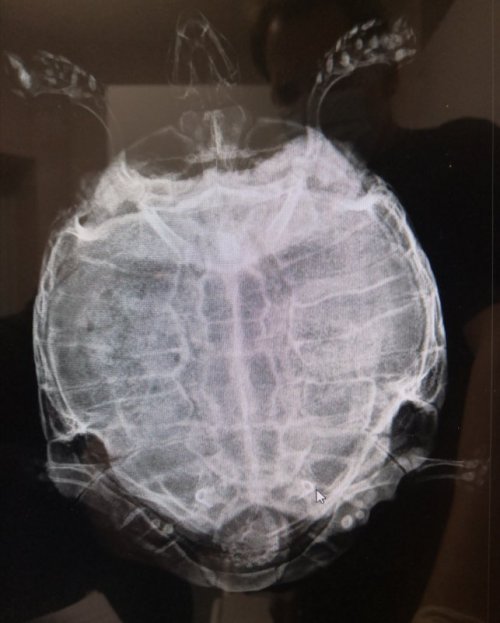

@Podolnyi  удалось сделать снимок, правда контраст отказались вводить, еле уговорила хоть такой((

IMG_20201027_205513.jpg

IMG_20201027_205724.jpg

Уролитов в мочевом пузыре я не вижу, но это не означает, что их не может быть там.